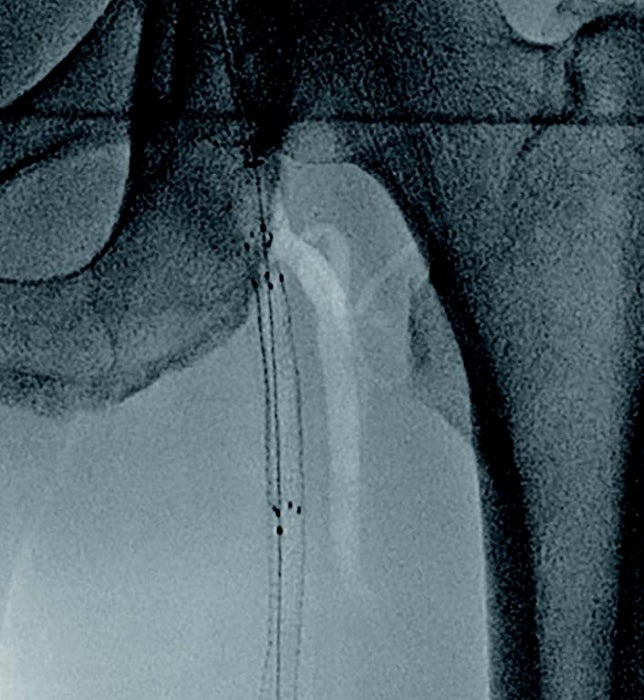

- IVUSにて遠位部のヘルシーな部分をマーキングし、バイアバーン® ステントグラフト径6.0/長250 mm を留置(図2)。

- 径6.0/長150 mm高圧バルーンにてP3 segmentの穿刺部止血を兼ね長時間拡張し、バイアバーン® ステントグラフト内を高圧拡張。

- 造影上は良好な血流改善を得られたが、IVUSではSFA起始部にプラーク残存を認めた(図3)。

- プラークをフルカバーするため、SFA起始部にバイアバーン® ステントグラフト径6.0/長50 mmを追加留置(図4)。

- 径6.0/長150 mm高圧バルーンにて高圧拡張を追加し、DFAの血流も問題がないことを確認して手技終了(図5)。